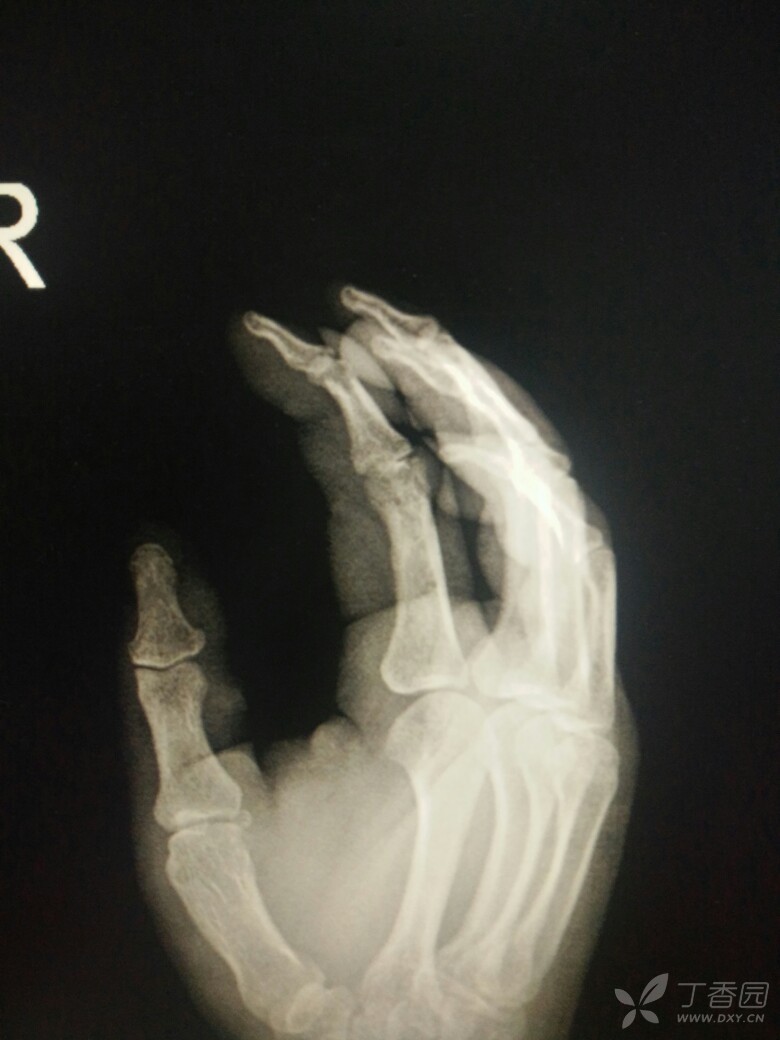

右手x片图片

右手x片图片,正常右手x光片

右手刀砍伤,,拍x片正侧斜位

手术前x光片 右手2,4指完全离断,第4指大部分挫灭.

x光片显示,患者右手环指离断